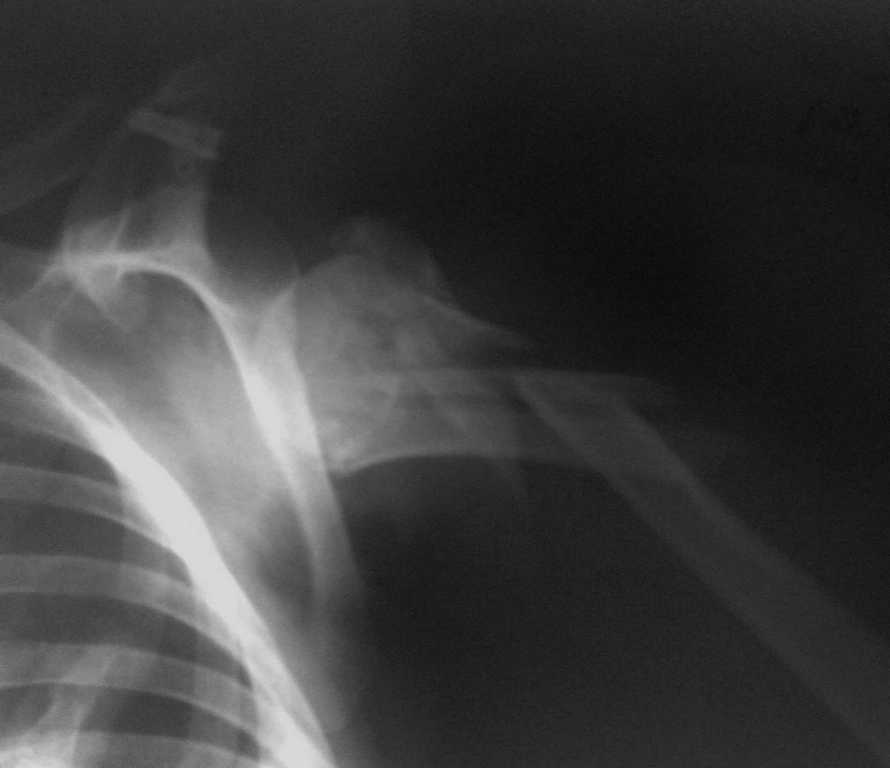

Уважаемые коллеги, хотелось бы узнать Ваше мнение о возможных вариантах оперативного

лечения перелома плеча. Пациентка, 51год, автодорожная политравма: закрытый двойной

перелом левого бедра (оперирован - Биос),полный внутрисуставной перелом проксимального

отдела левой голени (будет синтез LCP PLT на предстоящей неделе), переломо-вывих

проксимального отдела правого плеча. Травма от 08.01.2009